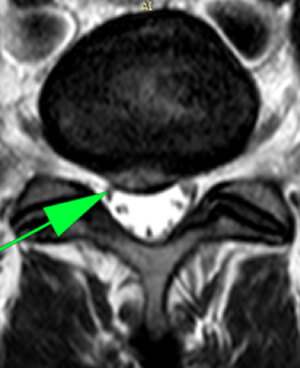

Резорбция грыж — это терапевтический процесс, направленный на уменьшение или полное исчезновение межпозвонковых грыж без хирургического вмешательства. Данный метод включает серию около 12 посещений клиники, три раза в неделю. После курса процедур, врач определяет время контрольного МРТ (обычно 2-3 месяца) для оценки результатов лечения.

Не все грыжи поддаются лечению данным методом. Решение о назначении резорбции принимается на основе анализа жалоб пациента, результатов МРТ и срока давности грыжи. Метод является безопасным и отличается отсутствием осложнений.

Кейс 1